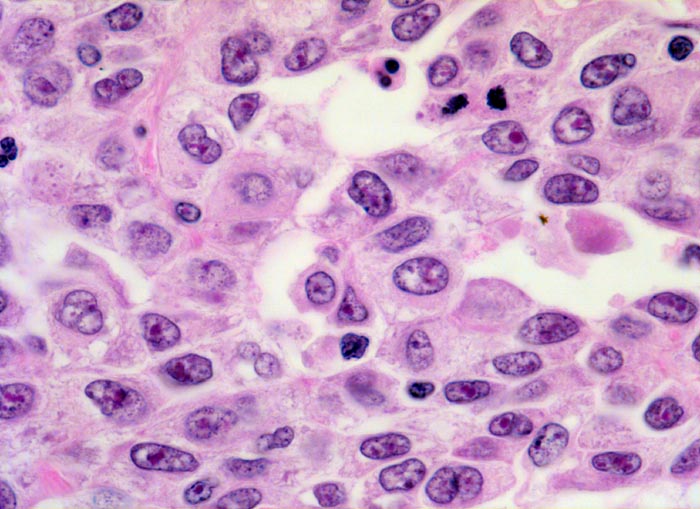

Morphologische Merkmale:

• Multiple Fragmente einer transurethralen Resektion.

• In der Mitte oben ist ein Harnblasenfragment mit tumorfreien Anteilen der Harnblasenwandmuskulatur erkennbar. Dieses Fragment ist bedeckt von einem aus wenigen Zellagen bestehenden dyskohäsiven Urothel, von dem sich einzelne Zellen ablösen. Die Zellkerne sind pleomorph, hyperchromatisch und vergrössert(Carcinoma in situ des tumorfernen Urothels).

• Fragmente eines papillär aufgebauten Karzinoms.

• Tumorzellkerne mit ausgeprägter Pleomorphie und Hyperchromasie sowie prominenten Nukleolen. Fehlende polare Ausrichtung der Tumorzellen. Zahlreiche Mitosen und Apoptosen.

• Kleinherdige Tumornekrosen.

• Invasion der Lamina propria (Tumorfragmente links): Kleine Tumorzellgruppen oder Einzelzellen haben die Basalmembran an wenigen Stellen durchbrochen und liegen in der Lamina propria.

• Begleitendes dichtes gemischtes Entzündungsinfiltrat.